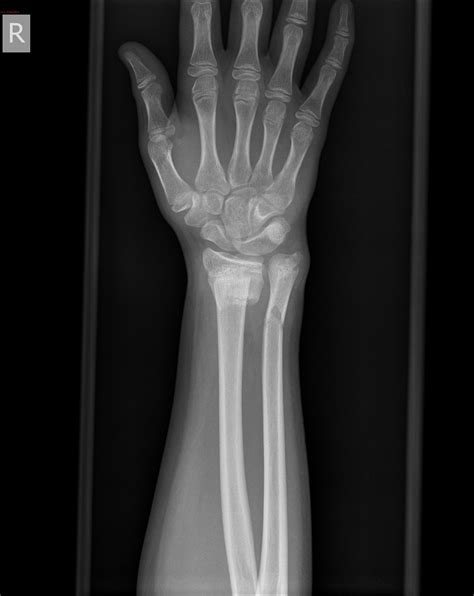

When you suffer an injury, the uncertainty of what lies beneath the skin can be the most stressful part of the recovery process. Whether you have taken a hard fall, been involved in an accident, or noticed persistent pain after physical activity, understanding the severity of your injury is the first step toward healing. An xray of broken bones remains the gold standard in diagnostic imaging, providing medical professionals with a clear map of your internal structure to determine whether a fracture has occurred and how best to align it for proper recovery.

An X-ray is a non-invasive medical imaging technique that uses a small amount of radiation to create images of the inside of your body. Because bones are dense and absorb more radiation than soft tissues like muscles or fat, they appear clearly as white or light gray shapes on the resulting image. When a bone is fractured, the continuity of that white structure is interrupted, creating a dark line or a visible gap known as a fracture line.

Medical professionals use the imagery from an X-ray to classify the injury. Understanding the terminology helps patients participate more effectively in their treatment plan. The table below outlines common fracture types frequently diagnosed through imaging.

Fracture Type Description

Transverse The break is a straight horizontal line across the bone.

Oblique The break is angled across the bone.

Comminuted The bone has shattered into three or more pieces.

Greenstick The bone bends and cracks but does not break all the way through (common in children).

Stress Fracture Tiny, hairline cracks caused by repetitive force or overuse.